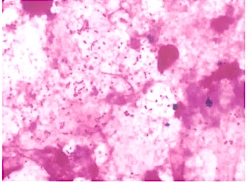

入院患者の喀痰です。

何がいるかわかりますか…?

答えはワタシデス!!バイオフィルム形成ちゅう♪

培養からはムコイド型の緑膿菌が検出されました。患者の気道内にバイオフィルムを形成した緑膿菌は粘性物質で菌体を包んで定着し、塗抹ではカエルの卵状に見え、培養ではM型集落が検出されます。